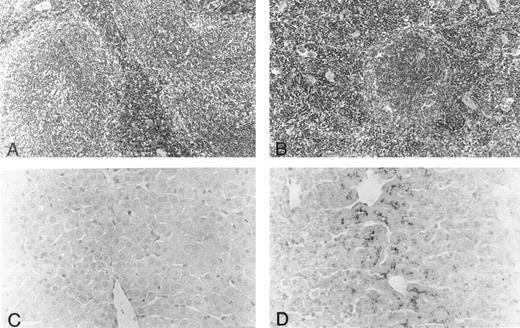

Histology.Body organs of fit1 mice appeared normally developed; however, fit1 mutant livers were detectably pale, and splenomegaly was present in most fit1 hemizygotes. Indeed, spleens from fit14397SB mutants composed an average of 1.87% ± 0.78 (n = 5) of the total body weight, whereas the mean weight of the normal littermate (cch +/cch +) spleens was 0.42% ± 0.09 (n = 5) of mean body weight (means are significantly different, P < .05). The spleens of fit14397SB mice had significant extramedullary hematopoiesis (EMH), characterized by a greater number of erythroblasts and poorly defined borders between the red pulp and white pulp, as opposed to the characteristic pattern seen in the spleens of wild-type mice (cch +/cch +) (Figs 2A and B). No EMH was seen in fit1 mutant liver (data not shown). Additionally, the fit1 mutant livers stained strongly for iron, compared with tissues from their wild-type littermates (Figs 2C and D). To a lesser degree, iron deposits were also observed in fit1 mutant spleens, and no iron deposits were seen in fit1 mutant bone marrow (data not shown).

Histology of spleen and liver from fit1 mutant mice. (A and B) Photomicrographs of hematoxylin and eosin-stained sections of (A) wild-type littermate (cch +/cch +) and (B) fit14397SB spleen. Erythroid precursors (darker staining cells) appear to be present in larger numbers in the fit1 mutant spleen, and in the mutant spleen, the white pulp areas appear smaller and less well defined. (C and D) Photomicrographs of Prussian blue stained sections from wild-type littermate liver (C) and fit14397SB mutant liver (D). Increased iron stores can be seen in the fit1 mutant liver as dark staining within several cells.